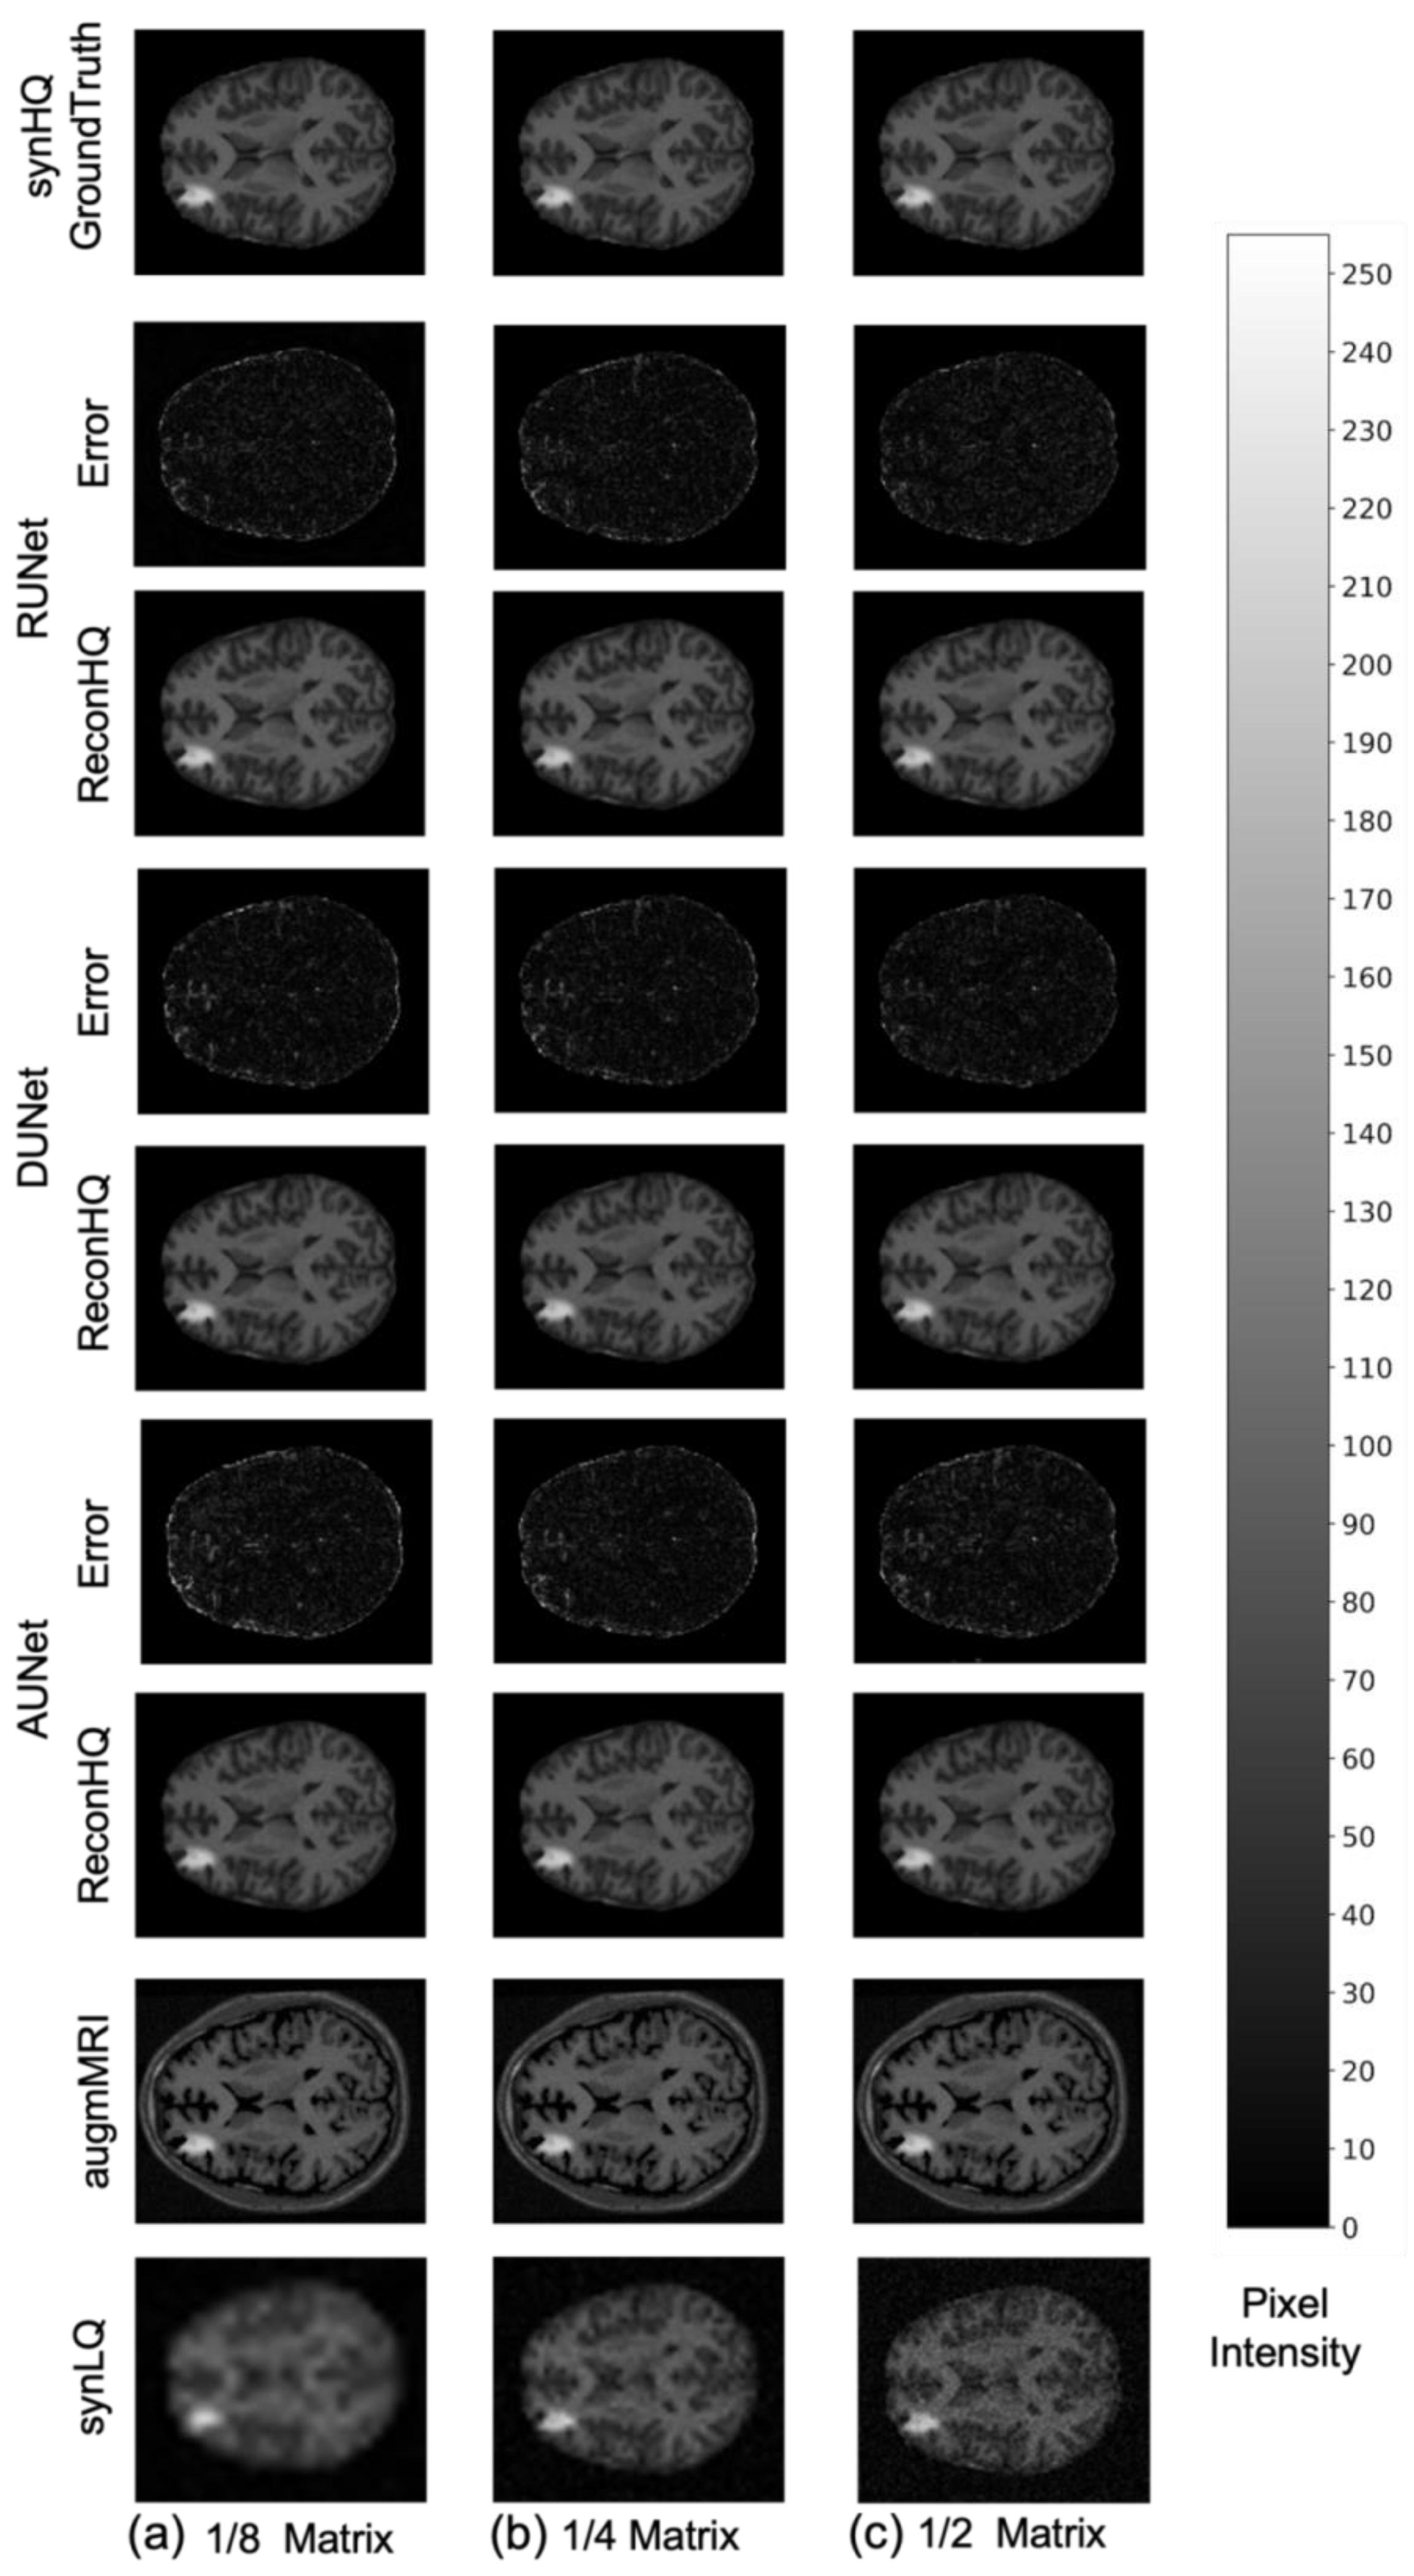

The performance of the UNets may also be appreciated in Figure 7 and Figure 8, which show the reconHQ images together with pixel-by-pixel differences with respect to the ground truth (i.e., |reconHQ—synHQ|) for the three networks at different synLQ sizes and two scanning scenarios. It can be observed that lesion reconstruction is better in the With-Prior compared to WithOut-Prior acquisition scenario for the 1/8 downsampled synLQ.

Figure 7.

Representative example of reconstructed images and errors versus ground truth with the three UNets trained for 100 epochs with the With-Prior acquisition scenario (i.e., including the augmMRI) to upscale (a) 1/8 downsampled (22 × 26) and (b) 1/4 downsampled (44 × 52) and (c) 1/2 downsampled (88 × 104) synLQ. The Error intensity in this figure is five times the original intensity.